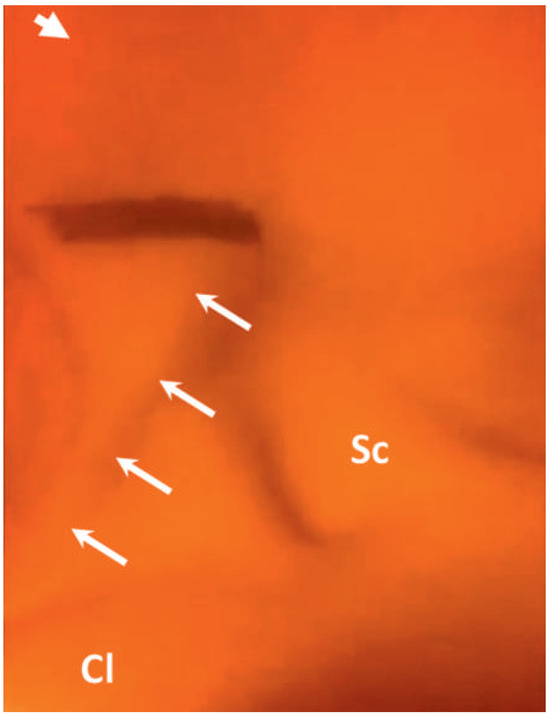

Kussmaul's Sign in Effusive Constrictive Pericarditis

by Mattia Cattaneo, Stefano Muzzarelli, Francesco Faletra, Alessandra Pia Porretta, Francesco Siclari and Augusto Gallino

Cardiovasc. Med. 2015, 18(1), 32; https://doi.org/10.4414/cvm.2015.00296 - 21 Jan 2015

A 67-year old man with mitral valve prolapse and moderate regurgitation was admitted because of dyspnoea, bilateral ankle swelling and hypotension. Close inspection of the jugular veins identified Kussmaul’s sign, a typical increase in the central venous pressure during inspiration (fig. 1; arrows) [...] Read more.

A 67-year old man with mitral valve prolapse and moderate regurgitation was admitted because of dyspnoea, bilateral ankle swelling and hypotension. Close inspection of the jugular veins identified Kussmaul’s sign, a typical increase in the central venous pressure during inspiration (fig. 1; arrows) [...]